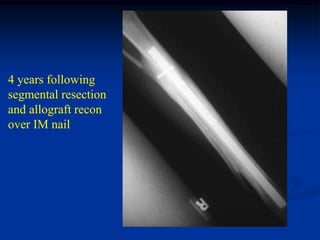

4 years following

segmental resection

and allograft recon

over IM nail